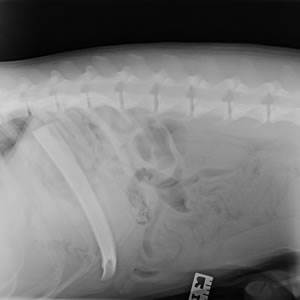

Chico, the dog with a ‘spare rib’

This x-ray of Chico the dog appears to show a ‘spare rib’. But the anomaly was actually down to the pet swallowing a six-inch cow rib bone whole!

Susie Hermit, Senior Vet at our Glasgow Shamrock Street Pet Hospital, said: “I’ve never seen an x-ray like it before, the position of the bone really did look like Chico had an extra rib!

“Amazingly he’d managed to swallow the bone whole but didn’t seem to be in any pain. However, we knew we had to carry out emergency surgery to remove it because it could have caused a life-threatening tear to his stomach or intestines.”